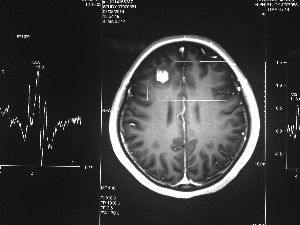

方框亮點(diǎn)為CT片顯示的異物

今年6月份,張敏在宿舍休息時,又發(fā)起了癲癇,也是口吐白沫,渾身抽搐。送到蘇州一家大醫(yī)院,頭顱核磁共振檢查出,張敏大腦右額葉處有一處病灶,也就是大腦額頭處有個東西。

腦袋里的東西,到底是腫瘤還是其他什么東西,這個謎像個石頭一樣,壓得張敏一家人喘不過氣。7月份,張敏一家又來到南京腦科醫(yī)院求醫(yī),第三次檢查后,醫(yī)生覺得很像是寄生蟲。不過,影像的檢查,只能作為醫(yī)生推測的依據(jù),具體是什么,只有手術(shù)拿出來后才能知道。